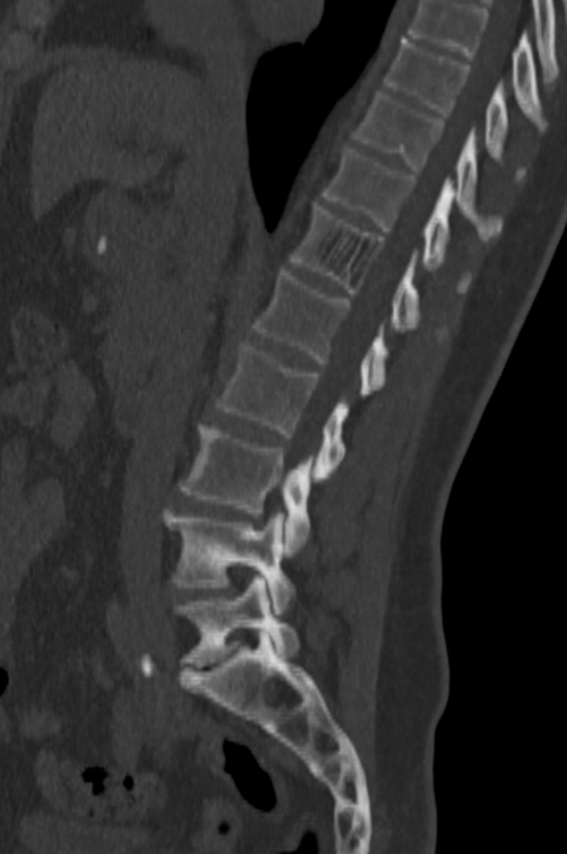

Vertebral haemangioma